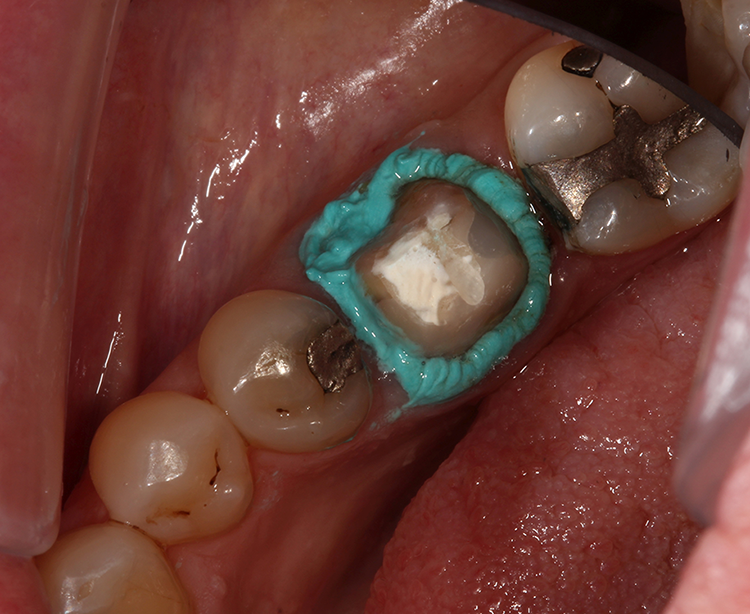

In der nächsten Sitzung wurde nach der Entfernung des Provisoriums eine gezielte Reinigung durchgeführt, gefolgt von der digitalen Abformung (Abb. 3). Zur Darstellung der Präparationsränder wurde vorbereitend ein Retraktionsfaden der Größe 000 mit einem Retraktionsfadenstopfer um den präparierten Zahn 46 gelegt (Abb. 4). Anschließend wurde zusätzlich VOCO Retraction Paste mit langsamen kreisenden Bewegungen in den Sulkus eingebracht und in situ belassen (Abb. 5 und 6).

Währenddessen wurde das Gebiet trocken gehalten. Nach 2 Minuten wurde die Retraktionspaste mit einem Luft-Wasser-Spray bei leistungsstarker Absaugung entfernt. Der Retraktionsfaden selbst wurde in situ belassen. Der Sulkus wurde luftgetrocknet.

Die klinische Situation mit einem erkennbar erweiterten, trockenen gingivalen Sulkus war ideal für den nachfolgenden intraoralen 3D-Scan (Abb. 7 und 8). Die CAD-Screenshots der mit dem Trios-Intraoralscanner (3Shape) erstellten 3D-Scans bestätigten den klinischen Eindruck (Abb. 9a und 9b).

Die provisorische Krone wirkt etwas unförmig (Abb. 2), was auf die mangelnde Ästhetik der ursprünglichen Krone zurückzuführen ist. VOCO Retraction Paste ist ein pastöses Produkt, das in einem Cap zur direkten Anwendung erhältlich ist. Es hat ausgezeichnete adstringierende Eigenschaften und hinterlässt, wie in diesem Fall zu sehen ist, einen trockenen und gut geweiteten trockenen Sulkus – ideale Voraussetzungen für eine hochpräzise Abformung.